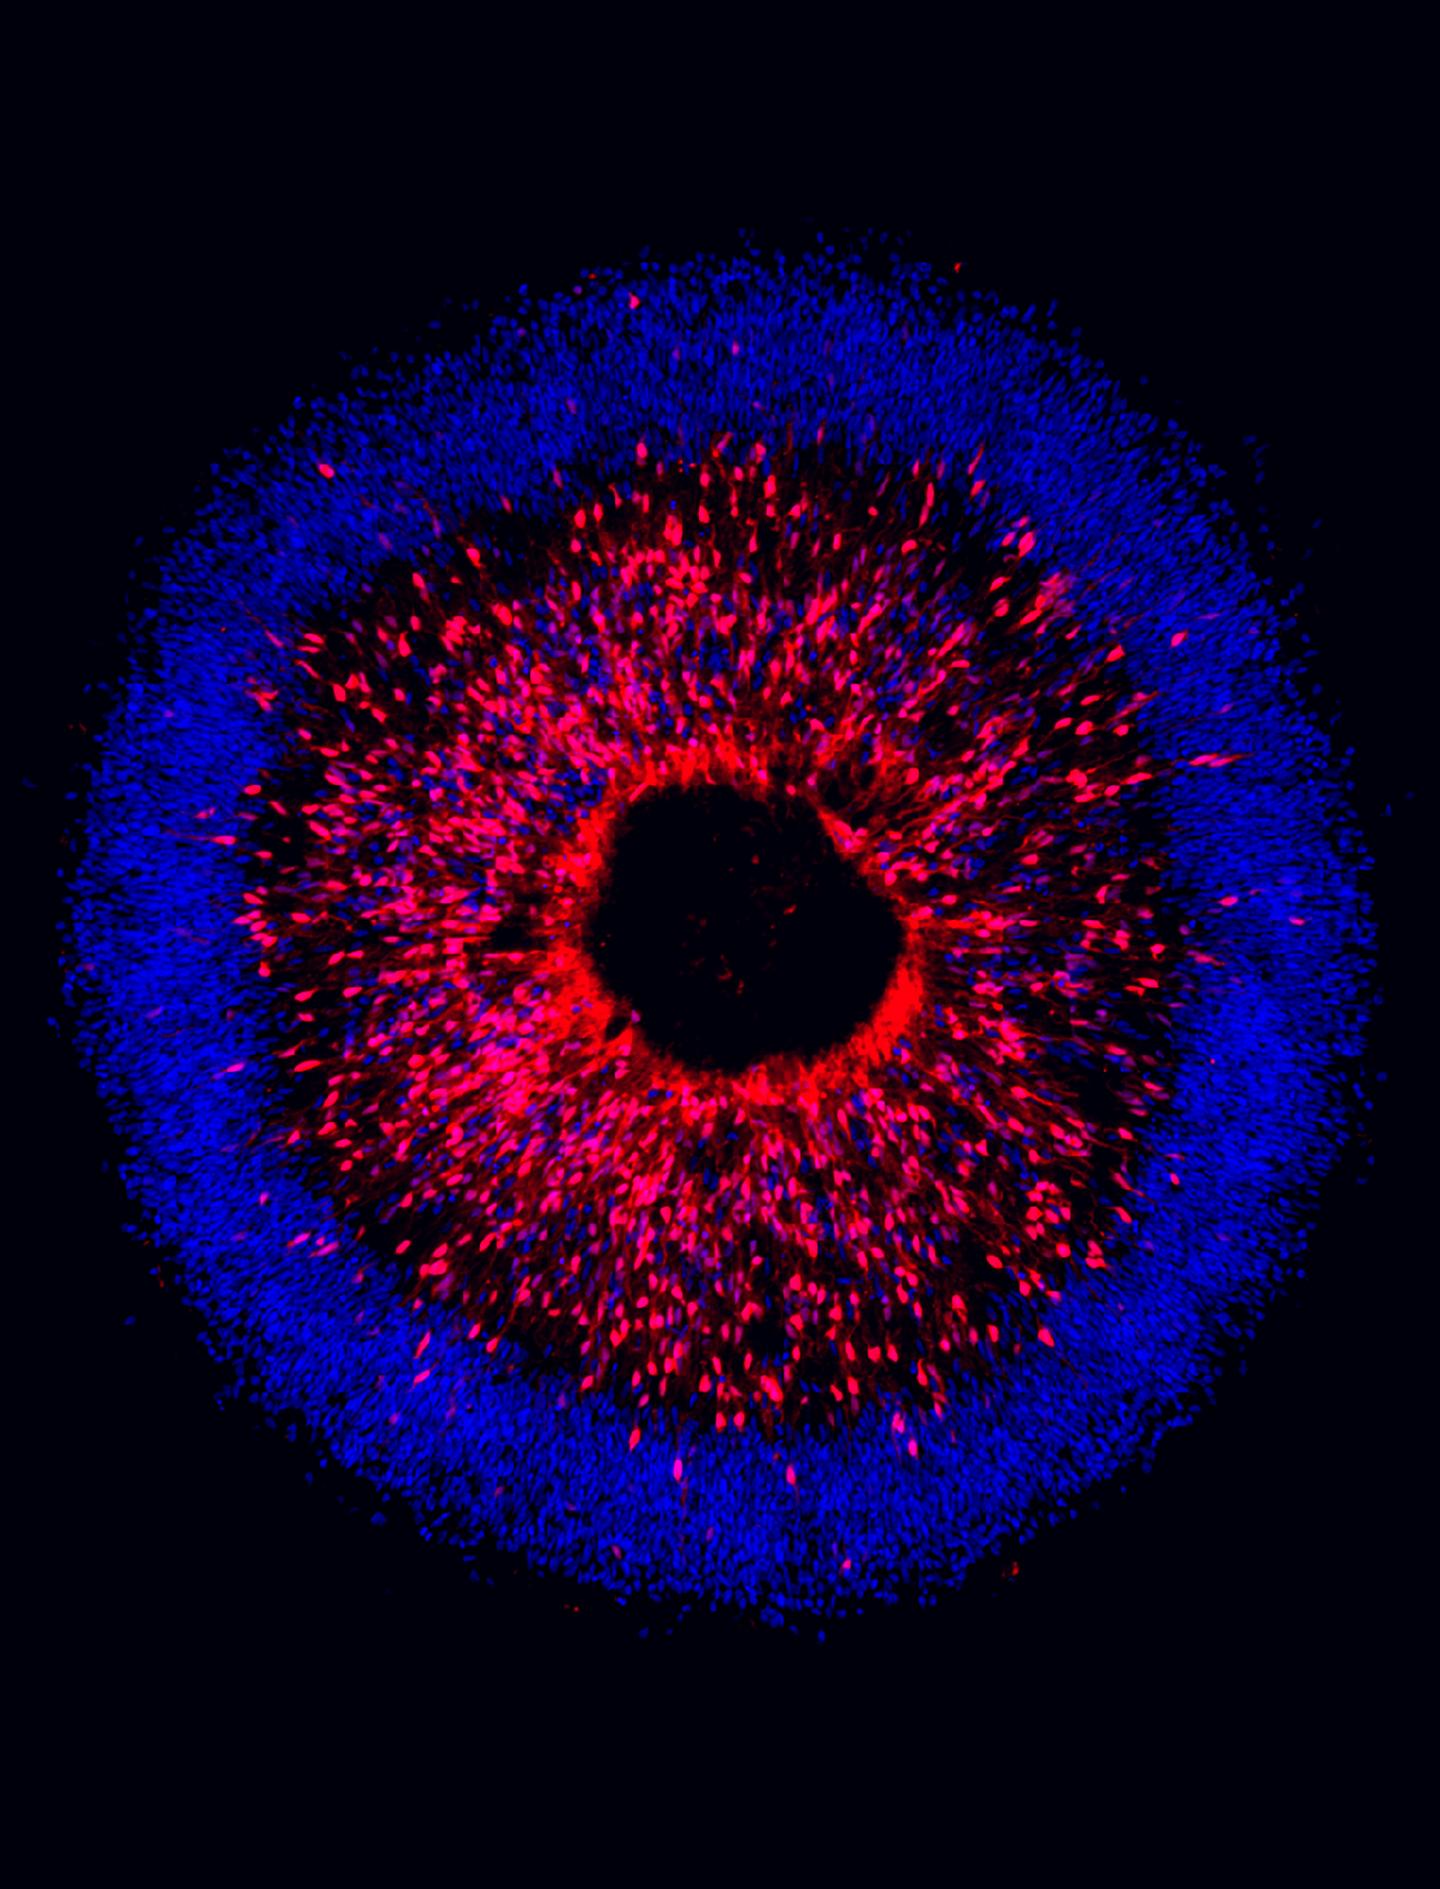

image: A team of researchers from IU School of Medicine are using human stem cells to study degeneration in glaucoma.

The study, published June 11 in Stem Cell Reports, focused on targeting genetic mutations within retinal ganglion cells, which serve as the connection between the eye and the brain. Researchers found that when differentiating pluripotent human stem cells into retinal ganglion cells, they were able to identify characteristics associated with neurodegeneration in glaucoma.

When retinal ganglion cells degenerate through glaucoma, it leads to the loss of vision and eventual blindness. Researchers in this study derived pluripotent stem cells from a patient that had a genetic form of glaucoma, Meyer said. They then differentiated the stem cells into retinal ganglion cells to search for neurodegeneration deficits.